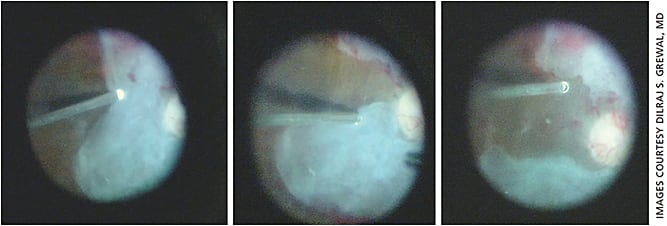

The mixed 23-27 mixed gauge vitrectomy, which utilizes the versatility of MIVS platforms, involves the passage of narrower gauge instruments through wider gauge cannulas.20 Initially, the larger 23-g probe is introduced and used to release anteroposterior traction and perform the core vitrectomy. The higher flow rate facilitates more efficient removal of the vitreous bulk.

The smaller 27-g probe is then introduced during the dissection of fibrovascular proliferation. It can be maneuvered more easily within tight dissection planes, especially the newer probe designs with a beveled tip (ULTRAVIT 10k probe, Alcon) which can act as a surrogate scissor with simultaneous active aspiration making it efficient for dissecting midperipheral and peripheral membranes in TRD (Figures 4-6).